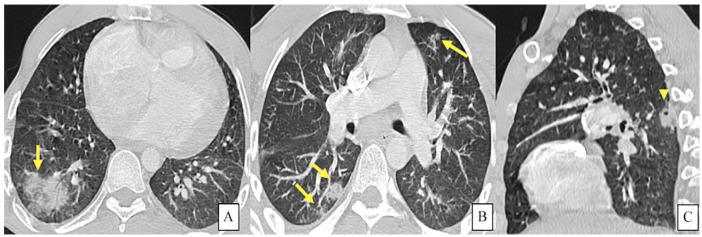

Case presentation: We present the case of a 32 year old male with known history of congenital ventricular septal defect presented to the emergency department with signs of sepsis and dyspnea. Blood cultures were positive for methicillin-sensitive Staphylococcus aureus. An echocardiogram found evidence of endocarditis with multiples intra cavitary vegetations. A CT angiogram demonstrated major right ventricular dilatation, multiple nodules and peripheral opacities, scattered throughout the lungs, indicative of septic emboli. Segmental saccular dilatation of the left lateral basal pulmonary artery consistent with a mycotic aneurysm formation was found. The patient was started on intravenous antibiotics and given the overall satisfactory evolution a conservative approach was pursued. The patient was discharged with antibiotics and scheduled for surgical repair of the ventricular septal defect.